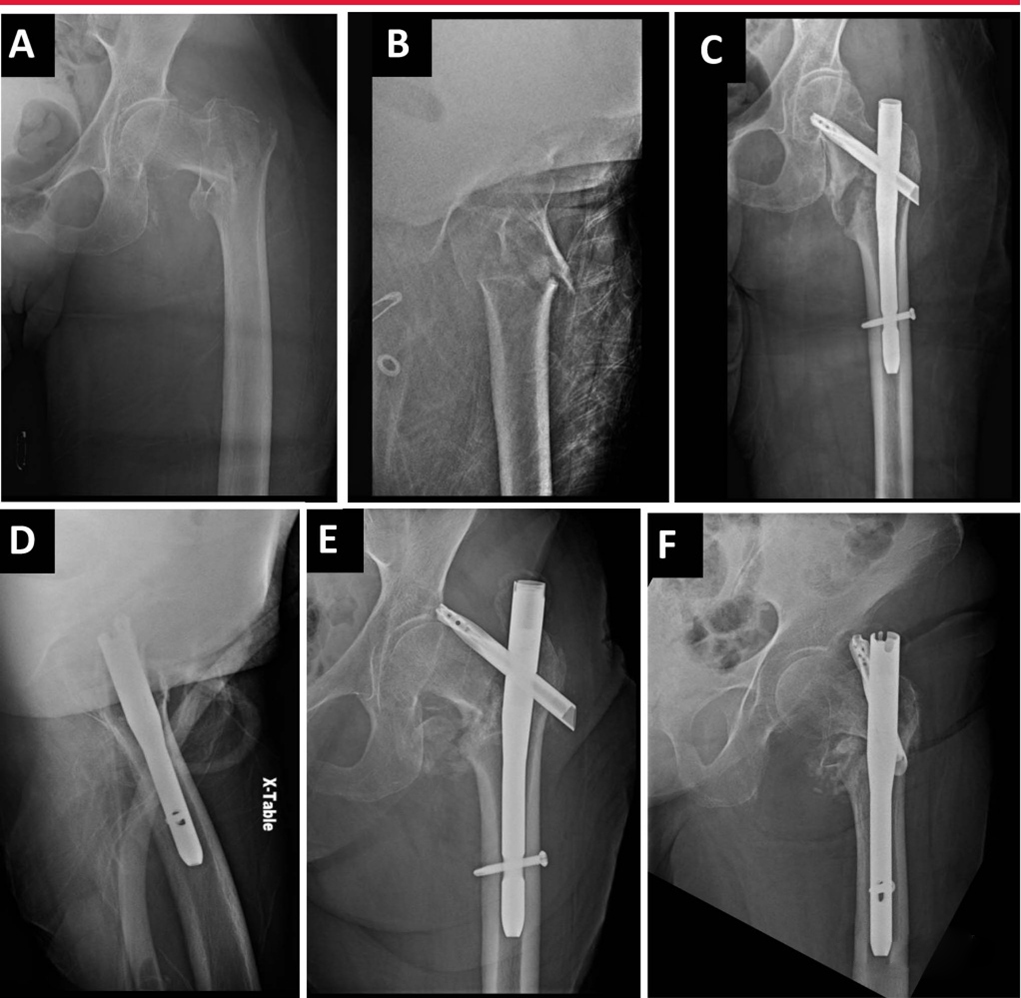

Оптимальное положение внутренней фиксации имеет решающее значение для поддержания редукции переломов и снижения риска неудачи внутренней фиксации. Отверстия, в частности, могут существенно повлиять на общее корональное и сагиттальное расположение переломов.Интрамедуллярные устройства для лечения околовертельных переломов могут привести к неправильной репозиции имплантата. Предпочтительный подход состоит в том, чтобы совместить длинную ось имплантата с осью бедренной кости, чтобы избежать неправильного варусного вправления, которое обычно находится медиальнее кончика вертела. Для совмещения с бедренным каналом в сагиттальной плоскости начальная точка должна находиться примерно на 5 мм кзади от верхушки вертела, чтобы обеспечить его смещение вперед. При подвертельных переломах особенно важно не начинать сагиттальную плоскость слишком кпереди. Биомеханические и клинические исследования в целом сходятся во мнении, что подходящее положение винта или спирального лезвия должно находиться в середине латерального положения, среднем или нижнем положении АП-позиции.

А, рентгенограмма: 74-летняя женщина с межвертельным переломом бедра слева. Б. На боковом снимке — оскольчатый межвертельный перелом бедренной кости. C: Послеоперационное AP-изображение показывает вальгусное уменьшение и неправильное расстояние между кончиками пальцев. D: Послеоперационное боковое изображение показывает большее расстояние между концами. E, AP-изображение через 6 недель после операции: коллапс варусной ткани и спиральный разрез лезвием. F: Боковой снимок через 6 недель после операции: разрез спиральным лезвием.